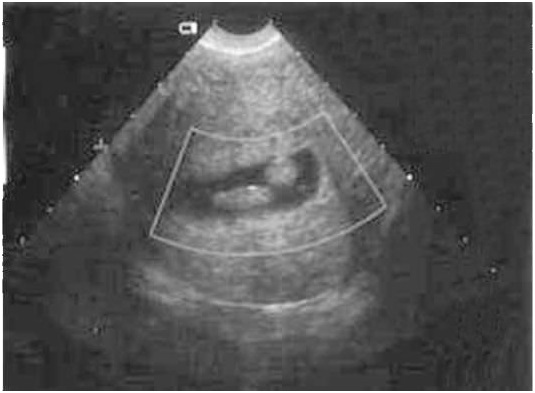

Изображение полипов на экране УЗИ

Полипы

Характерным проявлением эндометрических полипов является изоэхогенная структура. Но наличие в них фибриновых нитей увеличивает эхоплотность включения. На экране они похожи на эндометрий. При поперечном методе сканирования отличаются от эндометрических включений ровными круглыми контурами.